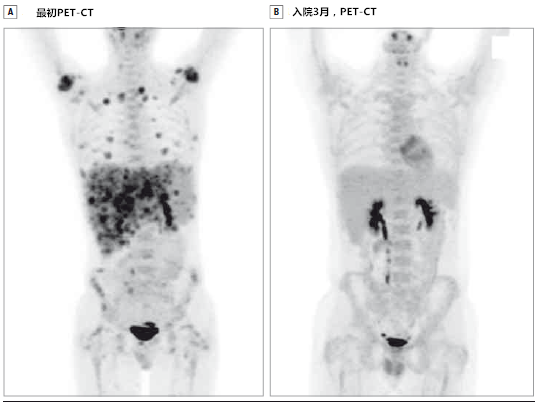

霍奇金**细胞淋巴瘤治疗前全身petct